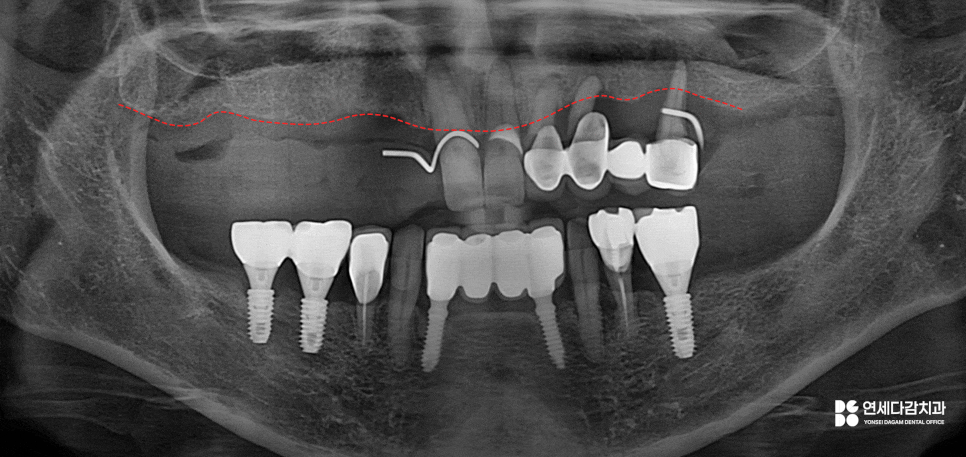

방사선 사진상

잇몸 라인이 불규칙하고

높낮이가 다른 양상을 보입니다.

또한 잔존 치아들을 평가했을 때

뿌리 끝만 잇몸 속에 남아 있는 상태인데,

이는 치아를 잡아줄 지지력을 잃은 환경으로

동요도가 심하게 나타날 수밖에 없습니다.

이렇게 치주 질환이 오래 방치한 경우에는

단순히 잇몸이 약해진 수준으로 끝나지 않습니다.

치근을 잡아주는 치조골도 손상이 되고,

발치 또한 고려할 수 있는 문제가 됩니다.